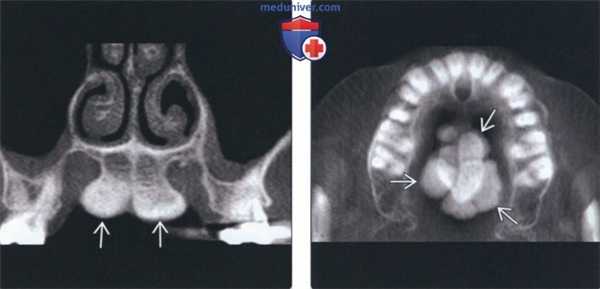

(Слева) На периапикальной рентгенограмме правой половины верхней челюсти у пациента с отсутствующими зубами определяются хорошо отграниченные рентгеноконтрастные наложения в верхних отделах верхнечелюстной пазухи, представляющие собой небный валик с фестончатыми краями. Визуализируется серповидное затенение (скуловой отросток верхней челюсти) и распространяющийся кзади рентгеноконтрасгный участок (нижний край скуловой кости).

(Справа) На корональной КЛКТ визуализируется маленький небный валик в средних отделах неба. Обратите внимание на небный экзостоз. Экзостозы часто сочетаются с небными валиками.

(Слева) На корональной КЛКТ визуализируется большой небный валик, разделенный посередине. Такие крупные валики могут приводить к нарушению функции и часто приводят к хронической травматизации, требуя удаления хирургическим путем. Покрывающая слизистая оболочка обычно истончена.

(Справа) На аксиальной КЛКТ у этого же пациента визуализируется мультицентрический небный валик. Обратите внимание на признаки доброкачественного роста: симметричное увеличение и ровные края.